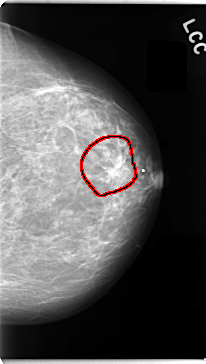

C_0059_1.LEFT_CC

FILE: C_0059_1.LEFT_CC.OVERLAY

TOTAL_ABNORMALITIES 1

ABNORMALITY 1

LESION_TYPE MASS SHAPE IRREGULAR MARGINS SPICULATED

ASSESSMENT 5

SUBTLETY 5

PATHOLOGY MALIGNANT

TOTAL_OUTLINES 1

BOUNDARY